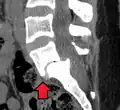

(A) CT sagittal view of a low grade slip.

(B) Lateral radiograph pre-operative intervention.

(C) Surgically treated with L5–S1 decompression, instrumented fusion and placement of an interbody graft between L5 and S1.

Both minimally invasive and open surgical techniques are used to treat anterolisthesis.[49]